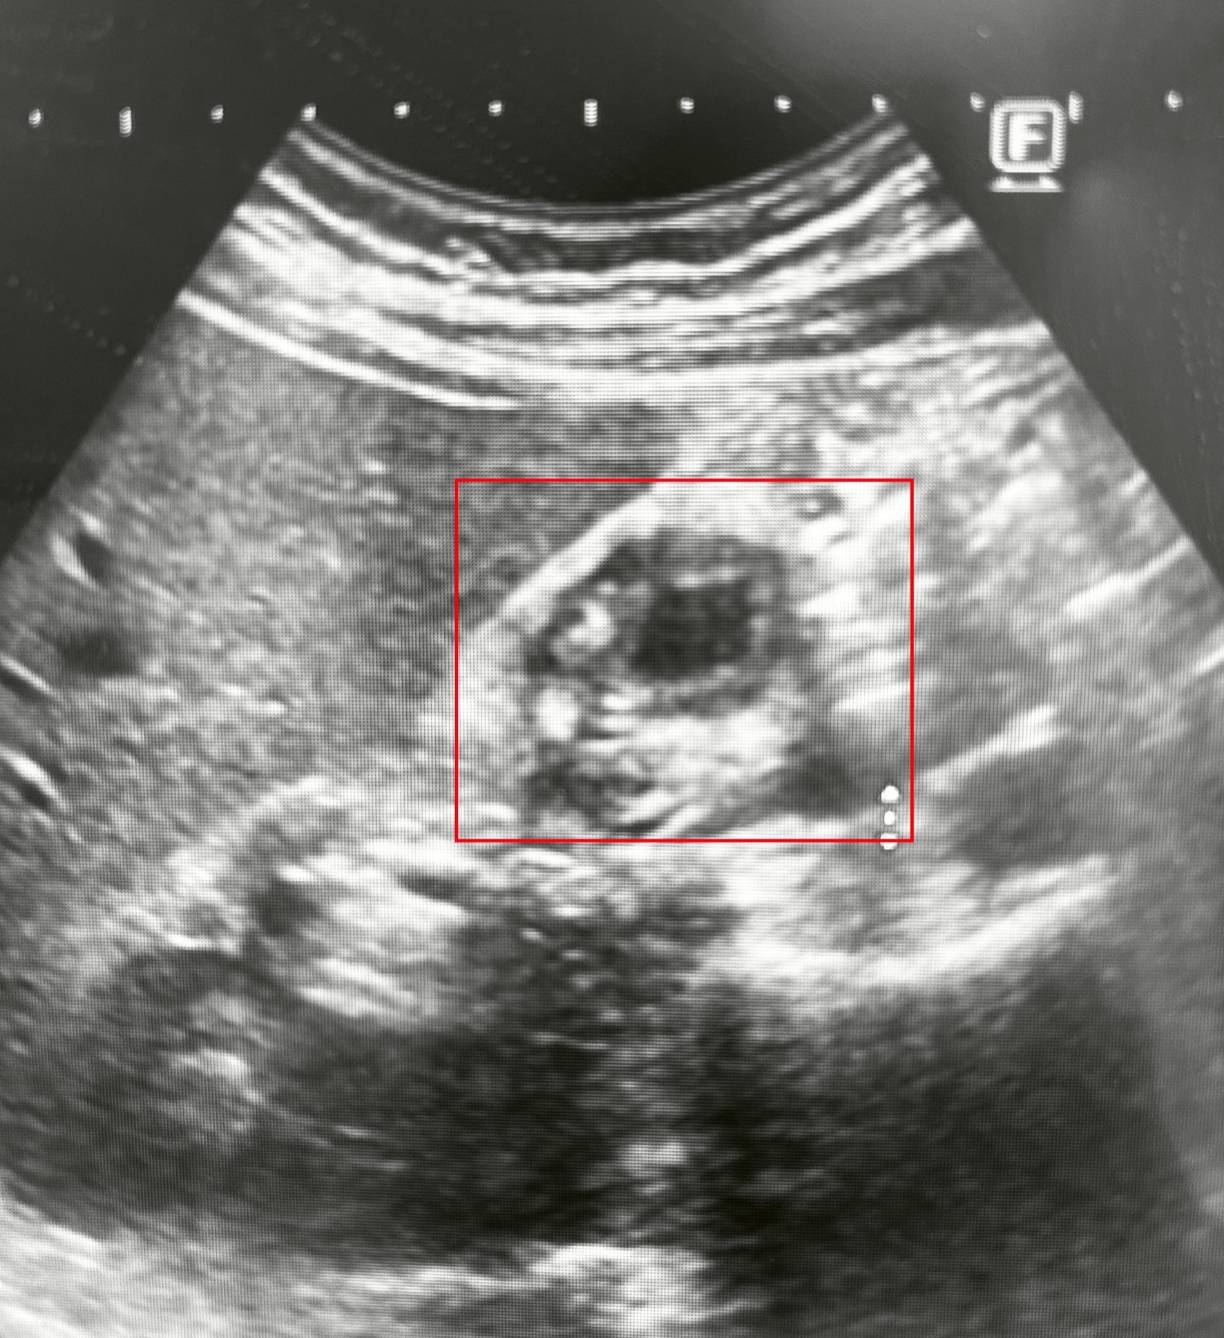

圖1:男子因心窩悶痛與右上腹脹痛,五年來四處求醫,近期至博田國際醫院肝膽胰外科看診並接受檢查時,才被發現罹患「膽囊腺肌症」。